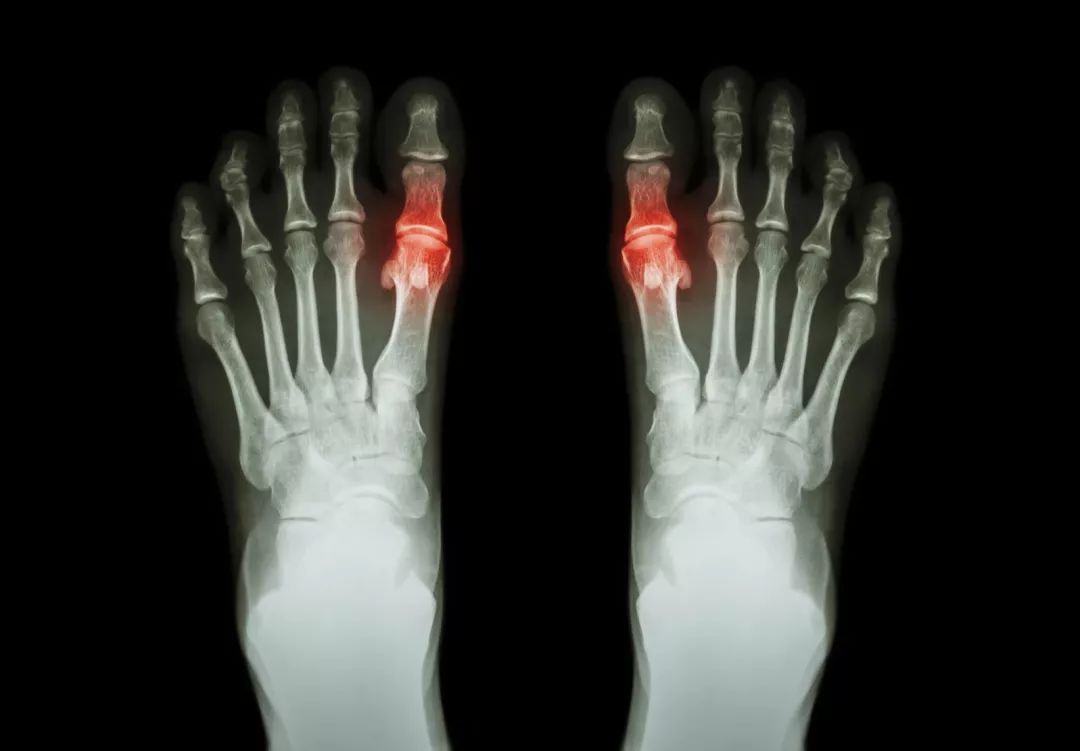

痛风是由于嘌呤合成代谢增加,尿酸产生过多;或尿酸排泄不良而致血中尿酸升高,尿酸盐结晶沉积在关节滑膜、滑囊、软骨及其他组织中,引起关节红肿热痛的无菌性关节炎,反复发作后会引起痛风石,造成关节损害,甚至功能丧失。